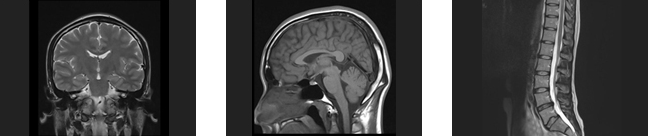

MRI検査

MRIとは、磁気共鳴断層画像診断装置(MagneticResonanceImaging)の略です。

X線検査やCT検査のようにX線を使わず、強力な磁石を埋め込んだトンネルの中に入り、電波を身体に当てることで体内の状態を断面像として撮影する事ができます。種々の撮像法の実用化により、コントラストのよい高精細な画像を比較的短時間に提供できるようになり、特に、脳・脊椎・四肢・骨盤腔(子宮、卵巣、前立腺)の病変に関しては、優れた検出能力を持っています。

CTとMRIの違い

CTはX線を、MRIは磁気を使って検査します。

それぞれ特徴がありどちらの検査を行うかは目的によって医師が選択します。